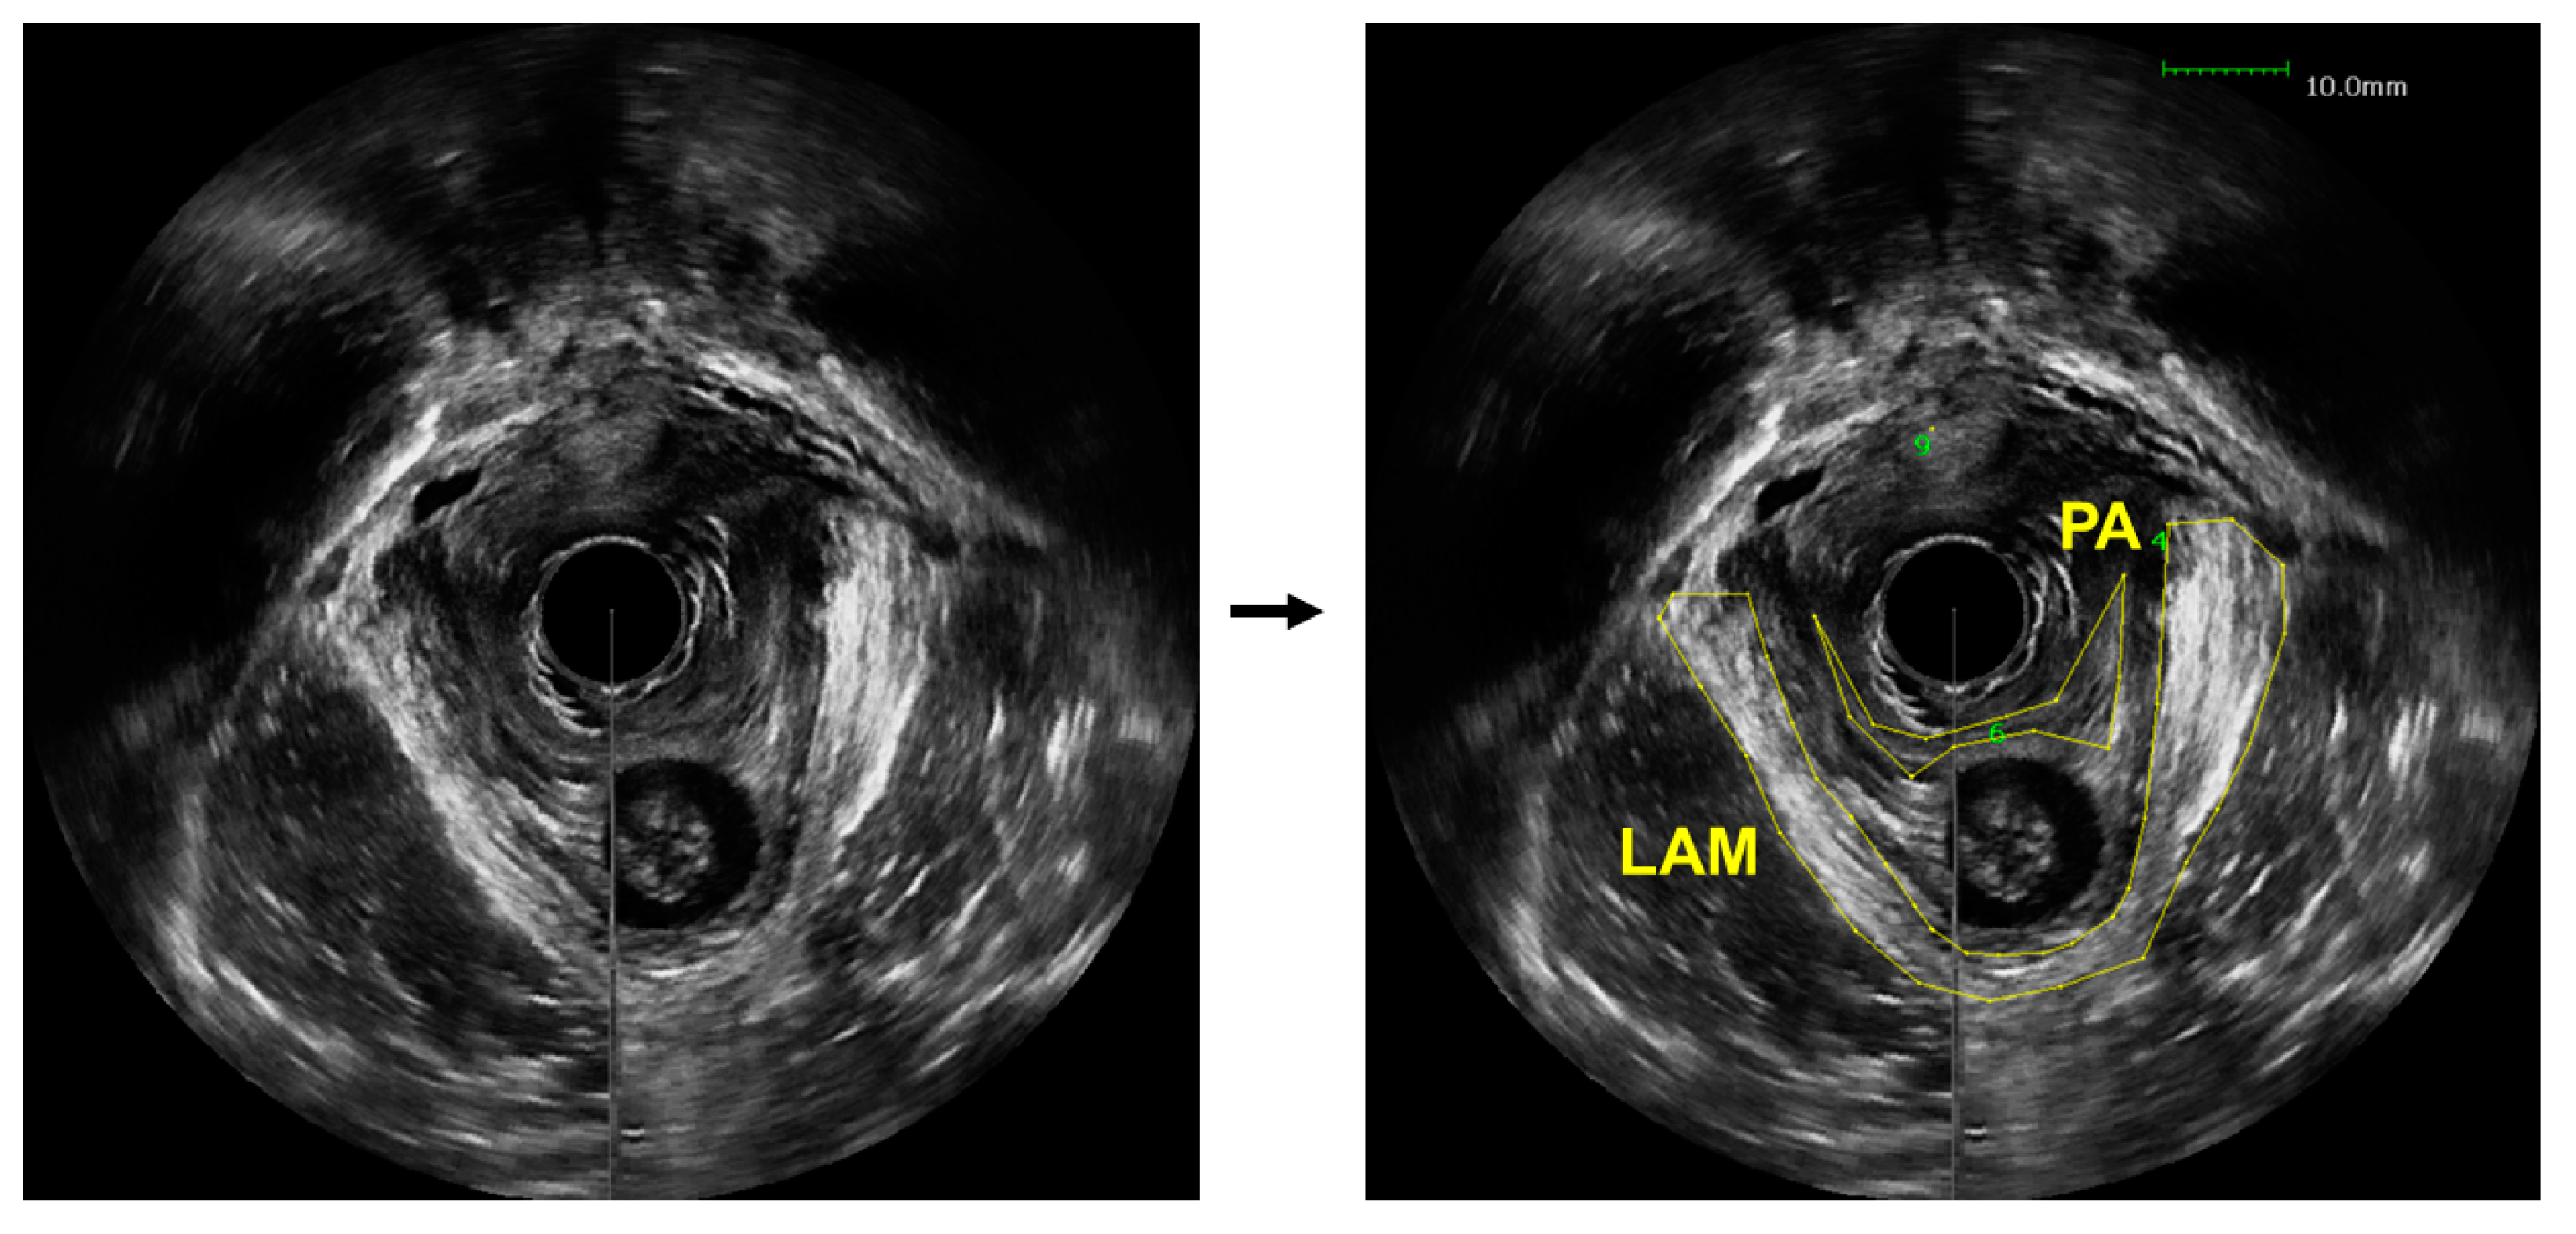

- Asif, Z.; Tomashev, R.; Peterkin, V.; Wei, Q.; Alshiek, J.; Yael, B.; Shobeiri, S.A. Levator ani muscle volume and architecture in normal vs. muscle damage patients using 3D endovaginal ultrasound: A pilot study. Int. Urogynecol. J. 2022. [Google Scholar] [CrossRef] [PubMed]